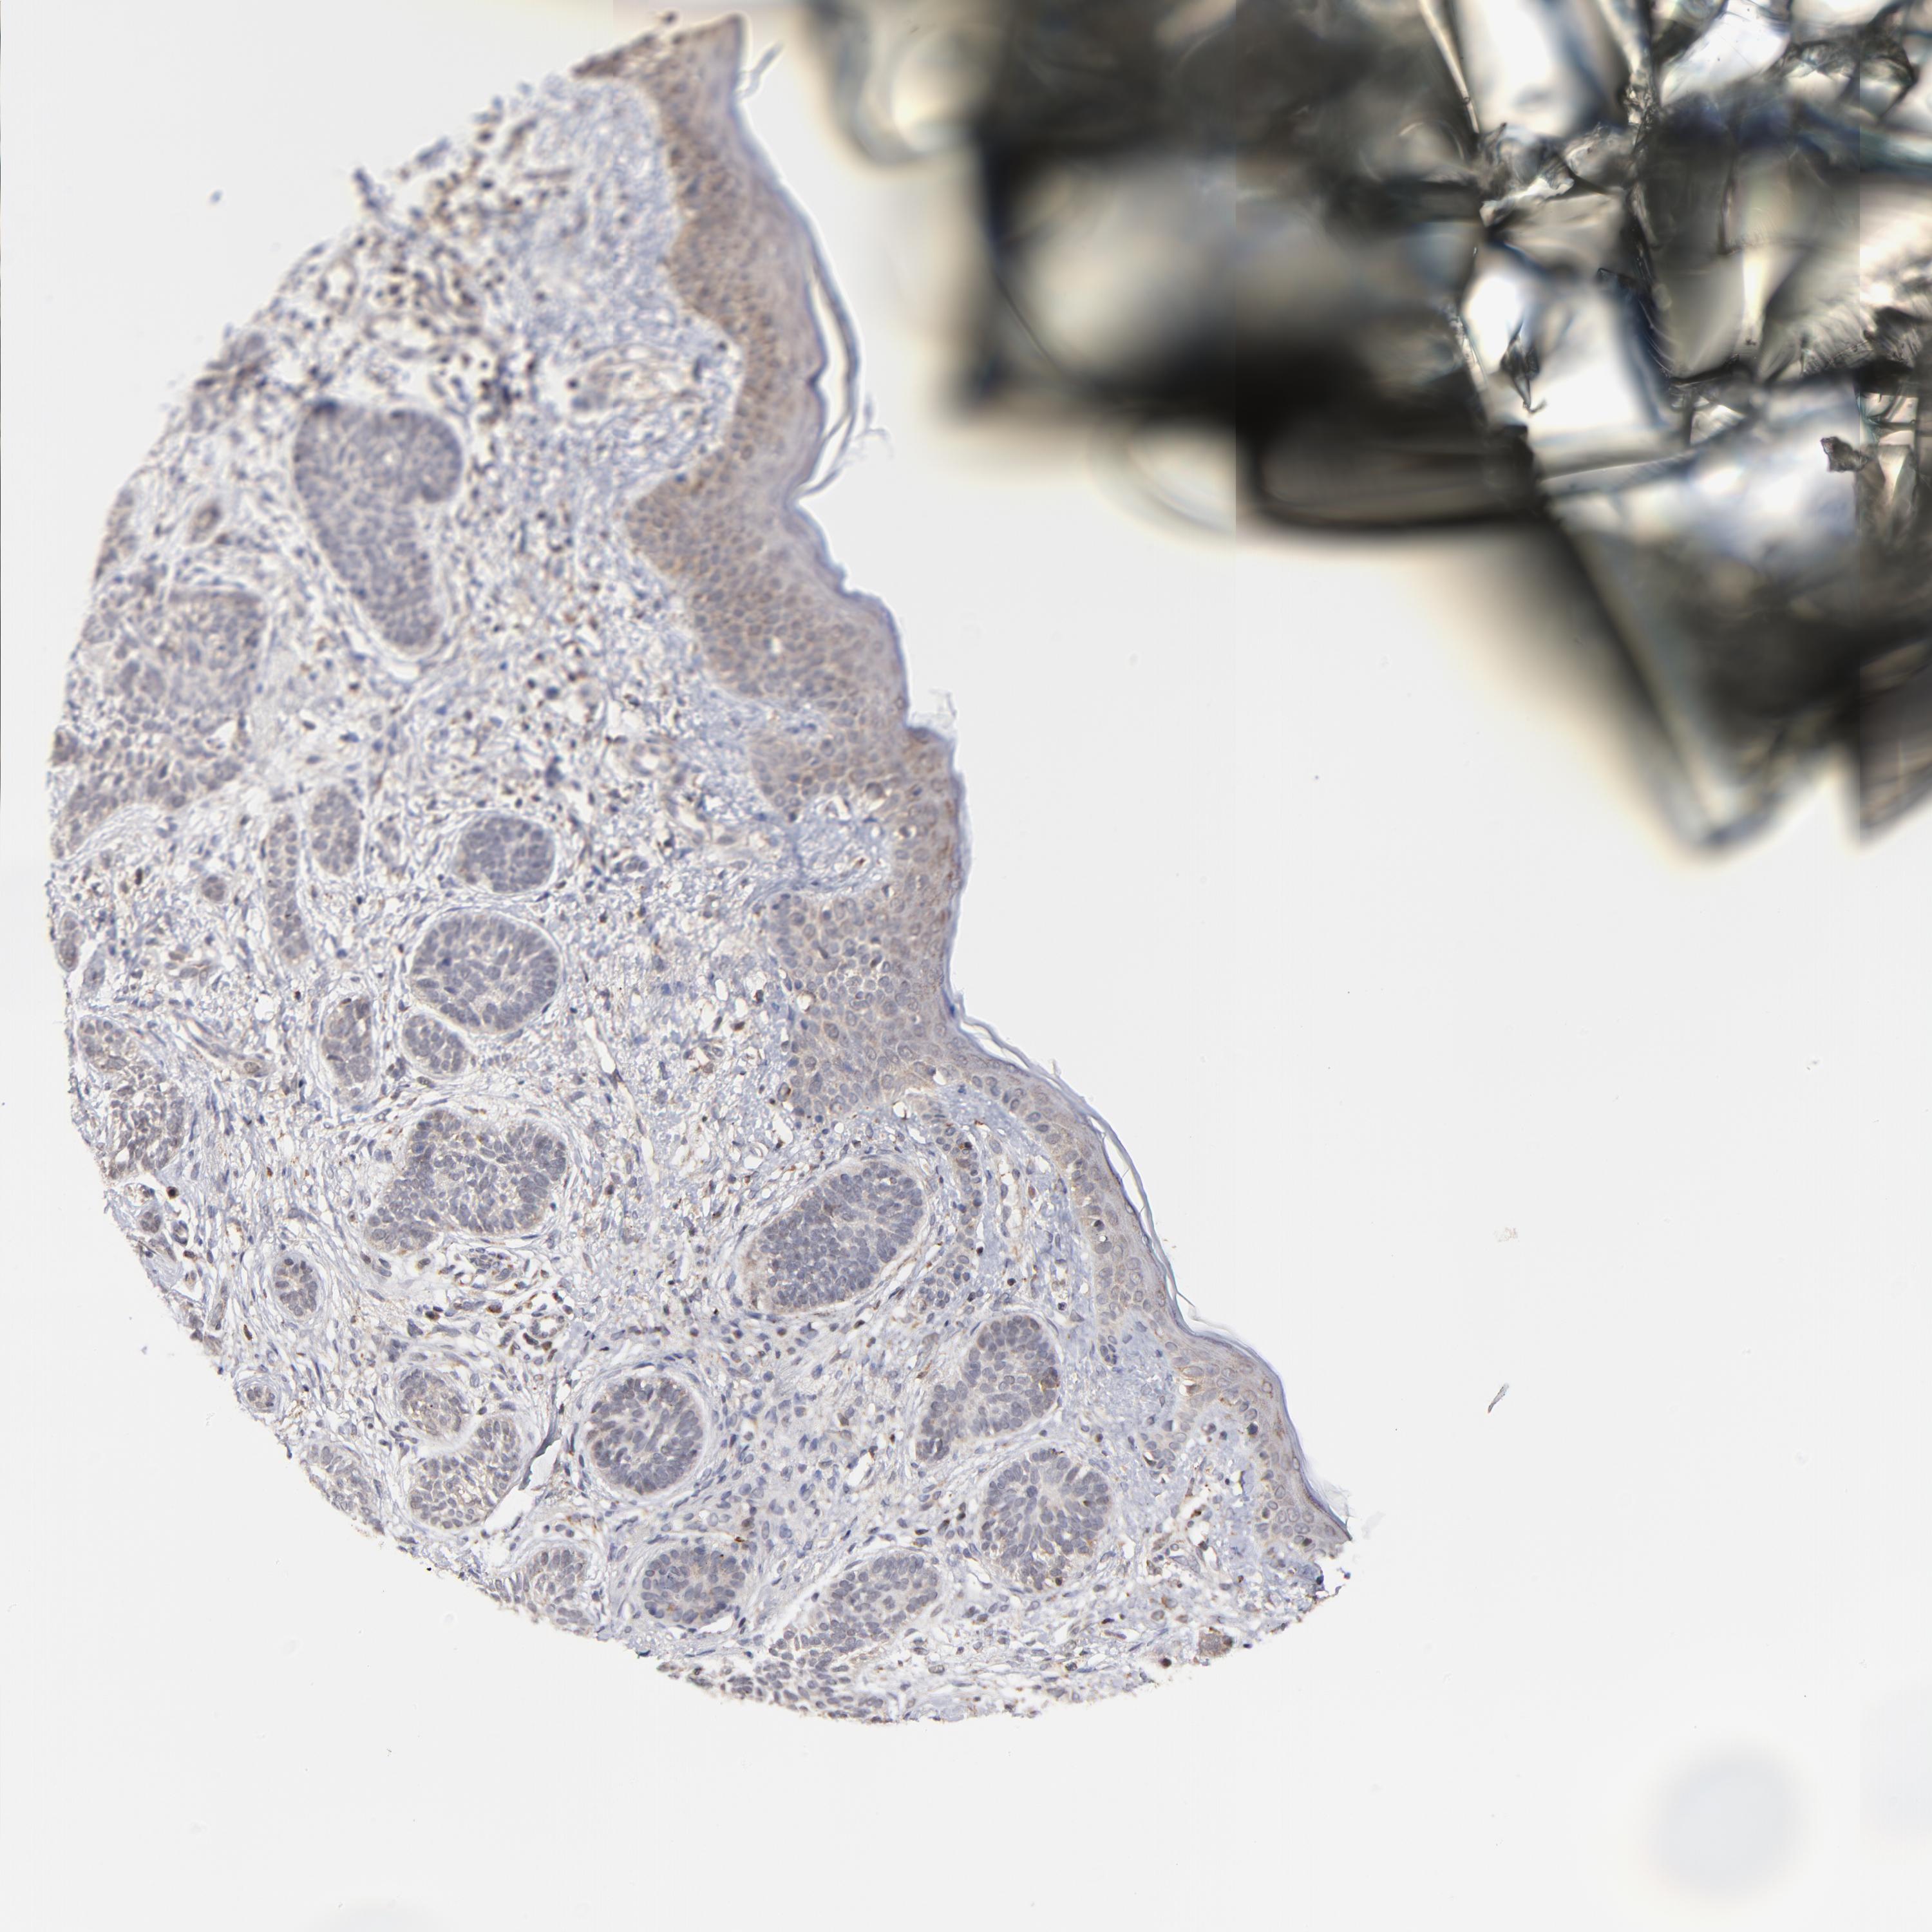

SKIN CANCER - Protein expressioni

A mouse-over function shows sample information and annotation data. Click on an image to view it in a full screen mode. Samples can be filtered based on level of antibody staining by selecting one or several of the following categories: high, medium, low and not detected. The assay and annotation is described here.

Antibody stainingi

Antibody staining in the annotated cell types in the current human tissue is reported as not detected, low, medium, or high, based on conventional immunohistochemistry profiling in selected tissues. This score is based on the combination of the staining intensity and fraction of stained cells.

Each image is clickable and will lead to virtual microscopy that enables deeper exploration of all samples and also displays staining intensity scores, fraction scores and subcellular localization as well as patient and tissue information for each sample.

Antibody HPA001633

Antibody CAB004262

Squamous cell carcinoma, NOS

Basal cell carcinoma